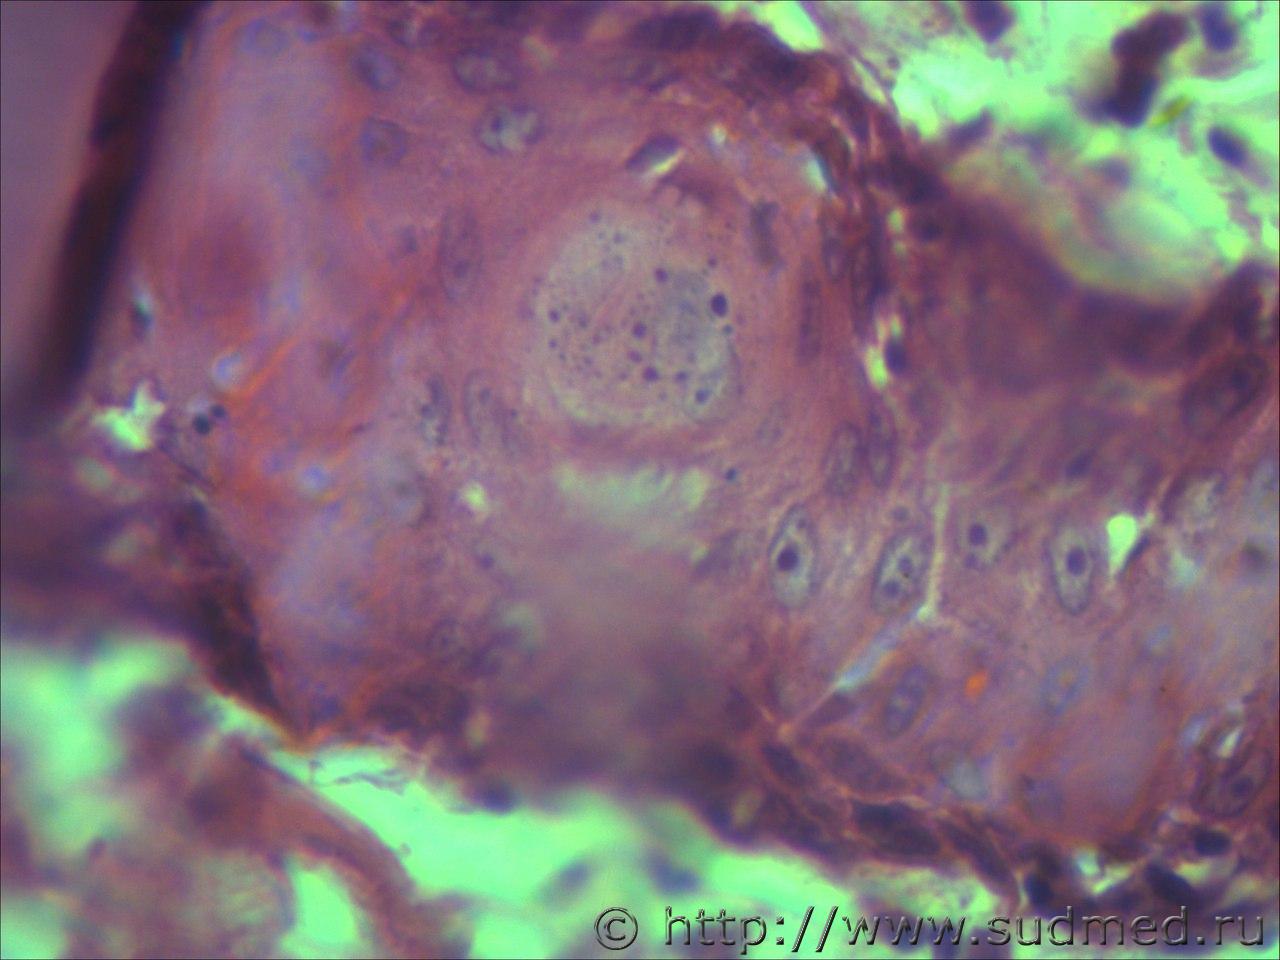

вижу что тяжи клеток эпидермиса проникающие в глубокие слои кожи и подлежащие ткани. Размеры клеток варьируют, слабовыраженное ороговение отдельных клеток, обильный воспалительный инфильтрат, пласты эпителиальных клеток в виде гнезд отделяются от эпидермиса. Склонен к ПКР

Попробую предположить,что на фото плазмоцитома и псевдокарциноматозная гиперплазия.